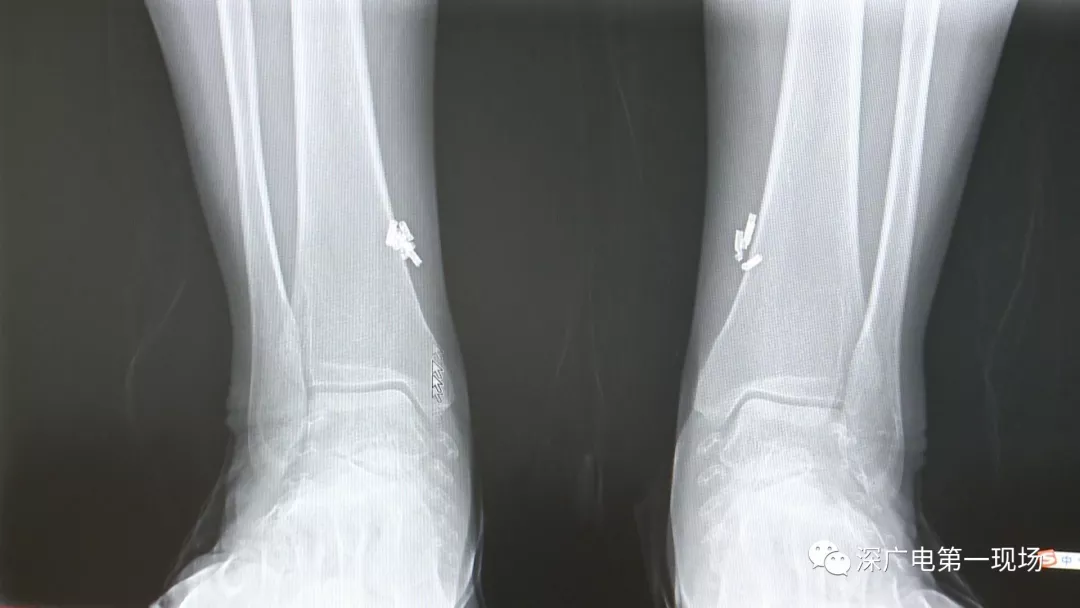

深圳一女子全身被植入彈簧圈,數(shù)量多到驚人!竟是為治這病…

出于保護患者,我們沒有直接采訪,但是通過醫(yī)生的介紹,記者了解到,病人是個36歲的女性,2歲開始就有癲癇病史,而且藥物治療也并不見效。

多方打聽之后,在山東某診所用全身埋彈簧圈的方式治療癲癇。陶主任介紹,這樣的方式想要治愈,那幾率也等同于撞大運?。?/p>